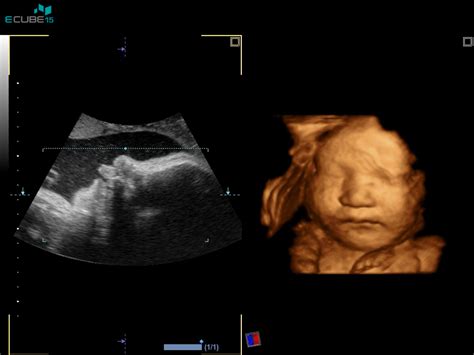

Pomembno je poudariti, da je spremljanje gibov ploda ključnega pomena. Če se vam zdi, da otroka manj čutite kot običajno, je priporočljivo, da se posvetujete z ginekologom. V primeru izrazite razlike v gibanju se opravi tudi ultrazvočni pregled ali snemanje srčnih utripov.